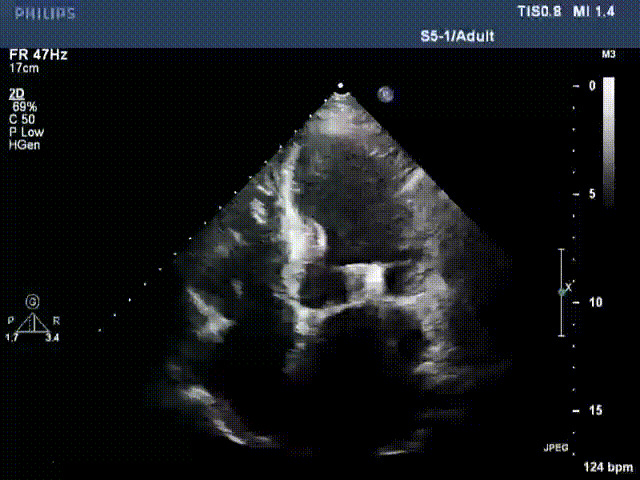

接受治療的是一例器質(zhì)性重度二尖瓣反流(DMR)患者,主訴“反復(fù)活動(dòng)后胸悶,氣促3年余”。術(shù)前超聲顯示,雙房增大,二尖瓣脫垂伴重度反流,輕度三尖瓣反流,輕度肺高壓,升主動(dòng)脈增寬。手術(shù)經(jīng)股靜脈-房間隔入路,采用全身麻醉插管,在TEE和DSA引導(dǎo)下完成房間隔穿刺。置入JensClip瓣膜夾系統(tǒng)后,在左房調(diào)整瓣膜夾的位置和軸向,后進(jìn)入左室,在TEE引導(dǎo)下捕捉二尖瓣前后瓣葉,并關(guān)閉瓣膜夾。經(jīng)TEE反復(fù)確認(rèn)手術(shù)效果后最終鎖定并釋放瓣膜夾。術(shù)后即刻超聲顯示瓣膜夾位置穩(wěn)定,功能良好,術(shù)前二尖瓣反流4+,術(shù)后0反流,肺靜脈逆流和左房壓都顯著好轉(zhuǎn),手術(shù)圓滿(mǎn)成功(以上數(shù)據(jù)都來(lái)源于醫(yī)院的臨床記錄)。術(shù)后患者狀態(tài)良好,目前已安排出院。

出院前隨訪(fǎng)超聲